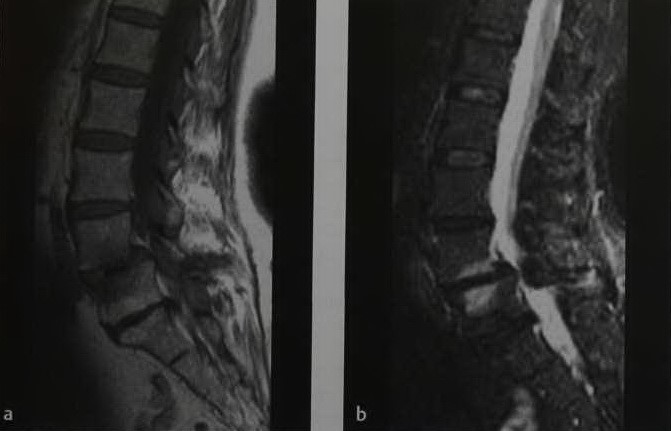

а, b Женщина 60 лет с эрозивным остеохондрозом (изменения соответствуют типу I по Моdic) L4 - L5. МРТ демонстрирует дегенеративный спондилолистез: (а) Т1-взвешенное изображение демонстрирует гипоинтенсивные полосы в костном мозге вдоль замыкательной пластины позвонка; (b) Изображение последовательности STIR с подавлением МР-сигнала от жировой ткани. Гиперинтенсивный сигнал костного мозга обусловлен отеком.